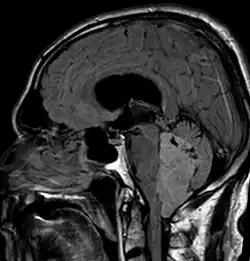

An ependymoma is a tumor that arises from the ependyma, a tissue of the central nervous system. Usually, in pediatric cases the location is intracranial, while in adults it is spinal. The common location of intracranial ependymomas is the floor of the fourth ventricle. Rarely, ependymomas can occur in the pelvic cavity.

Ependymomas make up about 5% of adult intracranial gliomas and up to 10% of childhood tumors of the central nervous system (CNS). Their occurrence seems to peak at age 5 years and then again at age 35. They develop from cells that line both the hollow cavities of the brain and the central canal containing the spinal cord, but they usually arise from the floor of the fourth ventricle, situated in the lower back portion of the brain, where they may produce headache, nausea and vomiting by obstructing the flow of cerebrospinal fluid. This obstruction may also cause hydrocephalus. They may also arise in the spinal cord, conus medullaris and supratentorial locations.[7] Other symptoms can include (but are not limited to): loss of appetite, difficulty sleeping, temporary inability to distinguish colors, uncontrollable twitching, seeing vertical or horizontal lines when in bright light, and temporary memory loss. It should be remembered that these symptoms also are prevalent in many other illnesses not associated with ependymoma.

Intracranial ependymomas, including supratentorial and posterior fossa, make up 90% of ependymomas in children. The supratentorial region is the upper brain region, or cerebrum, and contains the lateral and third ventricles. The posterior fossa, or infratentorial, is behind or below this region in the area of the brainstem and cerebellum and contains the fourth ventricle. A majority of intracranial pediatric ependymomas are in the posterior fossa.[15] Patients with intracranial ependymomas typically present with increased intracranial pressure that results in headaches, dizziness, nausea, and vomiting. The third location of ependymomas is within the central canal of the spinal cord. Spinal ependymomas comprise about 65% of adult ependymomas and most often occur in the lumbosacral region.[13] Patients with spinal ependymomas can present with back pain, numbness or weakness in the limbs, and urinary or bowel problems.